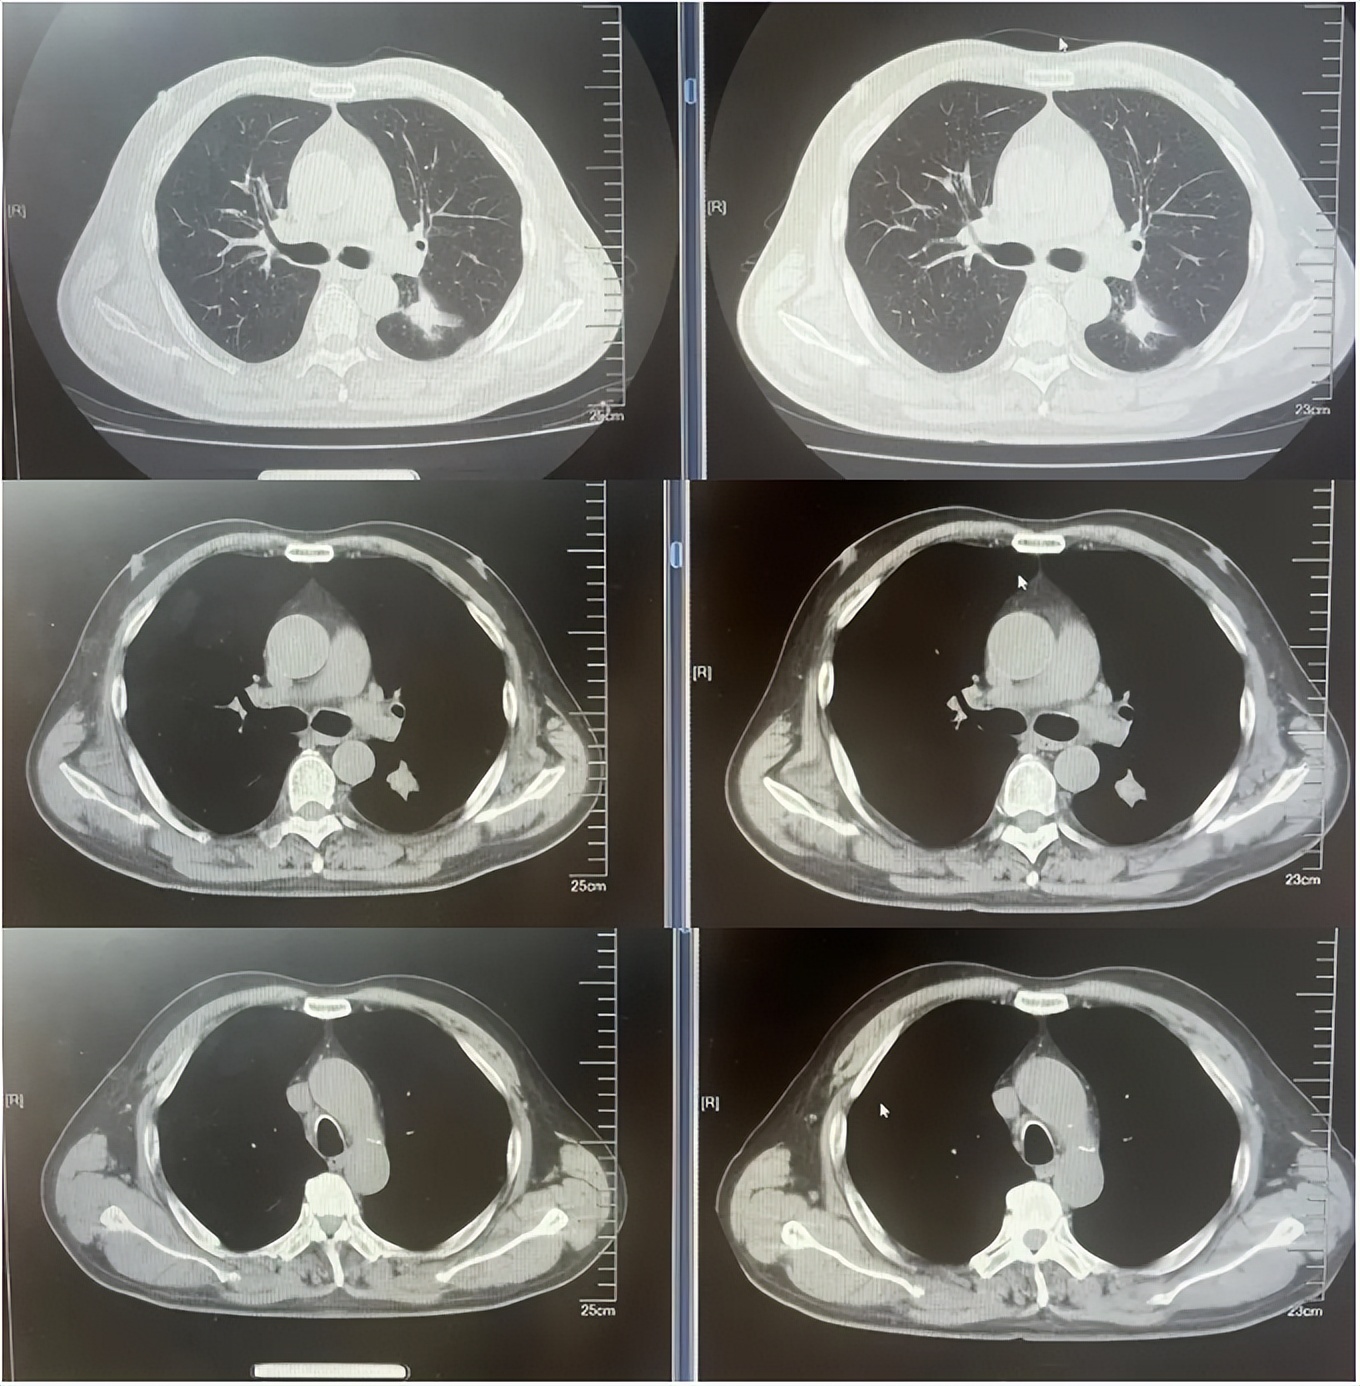

病例1:患者男,68岁。2024年6月以“胸闷气短1个月”为主诉于当地医院检查治疗。查CT提示左肺下叶肿物,纵隔、双肺门多发肿大淋巴结,左侧胸腔积液,左侧胸膜增厚。于当地医院行胸水穿刺引流查癌细胞提示肺腺癌。临床分期:cT2aN3M1a IVA期。患者于当地医院行血液基因检测未见敏感突变,使用AP方案化疗后病情进展。2025-1入我院后行肺穿刺活检,病例提示腺癌。行基因检测提示:ERBB2突变(丰度3.5%)。行德曲妥珠单抗(T-DXd)治疗至今。最佳疗效PR,目前持续有效中,PFS已超过7个月。患者使用德曲妥珠单抗期间出现II级恶心呕吐,经对症治疗可缓解。

德曲妥珠单抗治疗4周期(2025.5)疗效对比

德曲妥珠单抗治疗6周期(2025.7)疗效对比

德曲妥珠单抗治疗4周期(2025.4)疗效对比